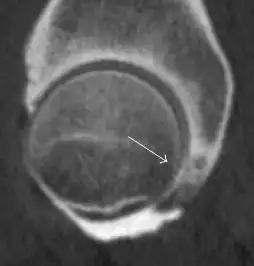

Synovial chondromatosis can be confidently diagnosed by X-ray when calcified cartilaginous chondromas are seen. However, other synovial proliferative processes, such as pigmented villonodular synovitis, require MRI for accurate diagnosis, although noncalcified synovitis can be suspected in radiographs by indirect signs, such as soft tissue swelling and/or erosions in the femoral head, femoral neck, or acetabulum (Figure 7).[1]

Figure 7:

-

Axial CT image of pigmented villonodular synovitis eroding the posterior cortex of the femoral neck.[1] -

Sagittal T2* gradient echo image showing a posterior soft tissue mass with hypointense areas secondary to hemosiderin deposition.[1] -

In synovial proliferative disorders, MRI demonstrates synovial hypertrophy. In the case of PVNS, characteristic foci of low signal intensity related to hemosiderin deposition are better seen on gradient echo T2* images (Figure 7). In the case of synovial osteochondromatosis, the synovial hypertrophy is accompanied by intermediate signal cartilaginous loose bodies and/or low signal calcified loose bodies.[1]